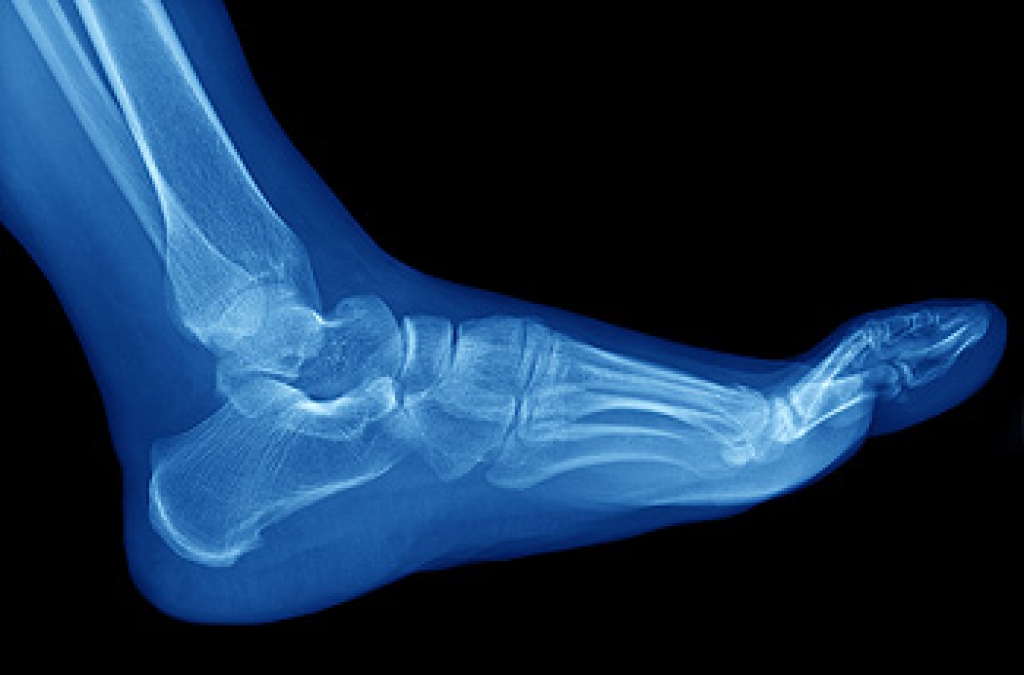

Exercise for your feet can help you gain strength, mobility and flexibility in your feet. They say that strengthening your feet can be just as rewarding as strengthening another part of the body. Your feet are very important, and we often forget about them in our daily tasks. But it is because of our feet that are we able to get going and do what we need to. For those of us fortunate enough to not have any foot problems, it is an important gesture to take care of them to ensure good health in the long run.

Some foot health exercises can include ankle pumps, tip-toeing, toe rises, lifting off the floor doing reps and sets, and flexing the toes. It is best to speak with Our doctor to determine an appropriate regimen for your needs. Everyone’s needs and bodies are different, and the activities required to maintain strength in the feet vary from individual to individual.